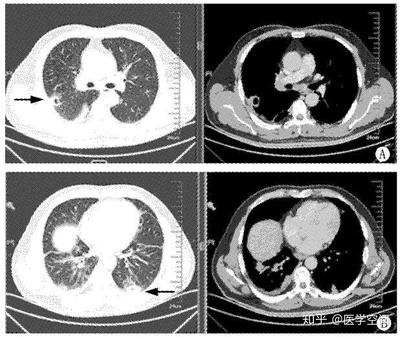

另外,生气的人更容易导致免疫功能低下,免疫功能受损,容易引起肺结节。那么中医如何解决这种“气怒”的肺结节人群呢?分享几个案例。案例1:马先生,65岁,吸烟30多年。2020年7月,因胸闷、胸痛、憋气等症状到医院就诊。CT检查后显示双肺多发结节。左肺下叶胸膜下有较大的实性结节,直径约6 mm,未给予其他治疗。